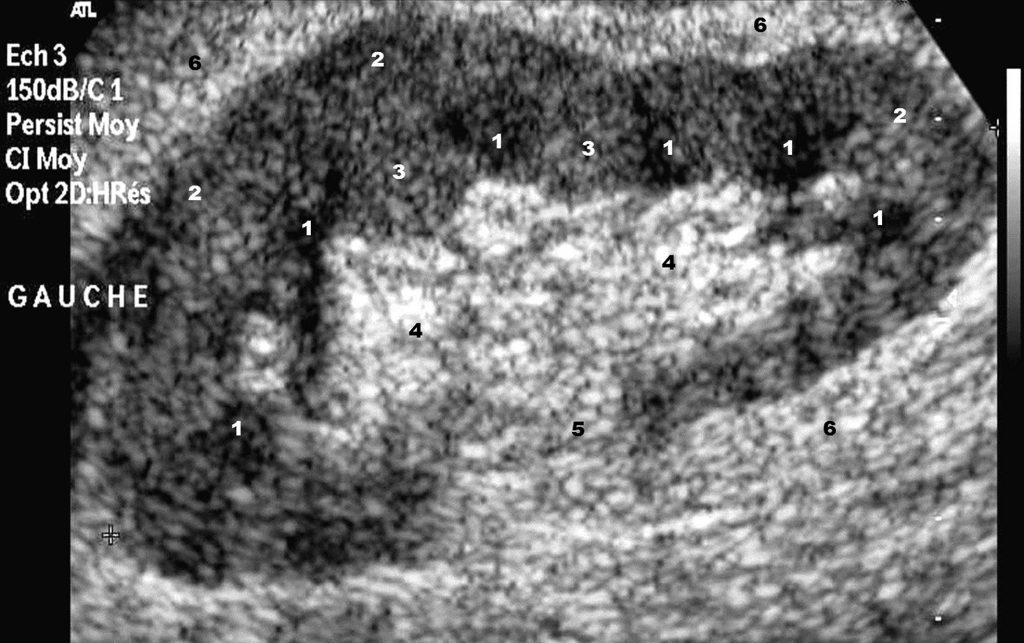

Fig. 19.3. Échographie rénale : coupe longitudinale du rein gauche.

1. Médullaire rénale (pyramides de Malpighi). 2, 3. Cortex rénal. 3. Colonne de Bertin. 4. Sinus du rein. 5. Hile du rein. 6. Espace périrénal.

Source : CERF, CNEBMN, 2022.